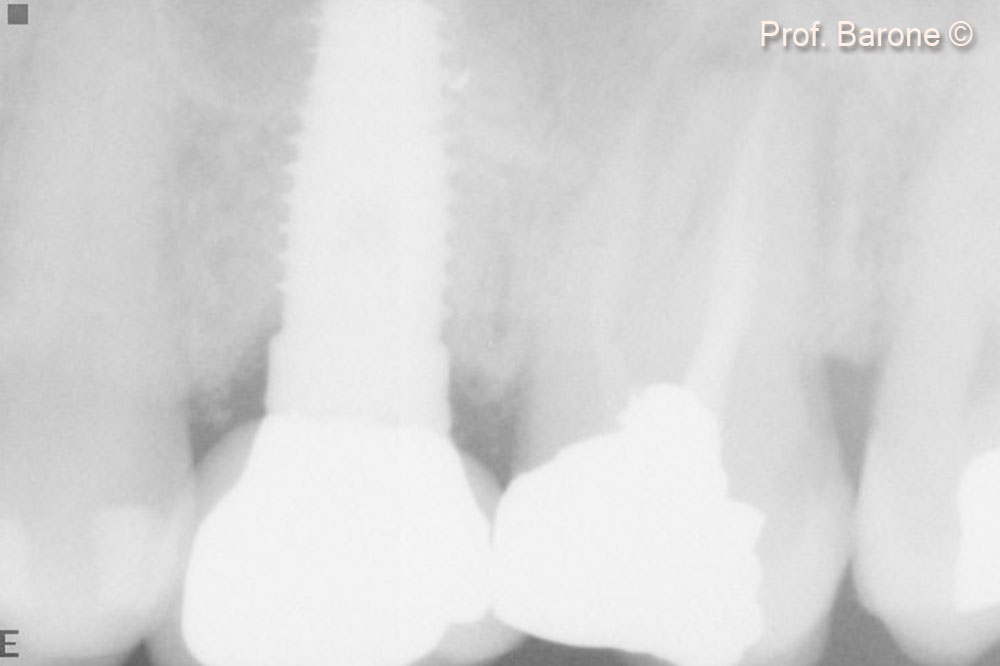

Hình ảnh X-quang quanh chóp răng ngay sau khi cấy ghép implant